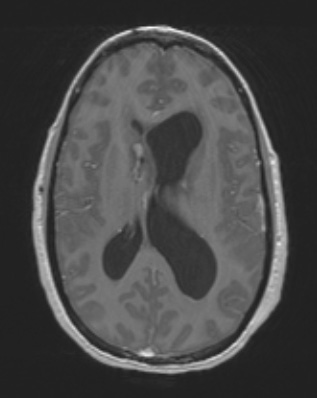

2A2 HGAP (Case 2) T1W - Copy

There is minimal enhancement on this T1-weighted scan with contrast.